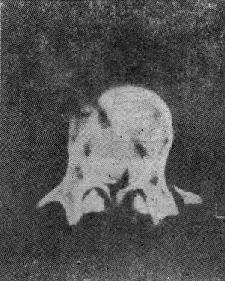

(三)爆裂型骨折 是由沿身体纵轴作用的暴力造成的骨折。椎间盘被压入椎体终板,进入松质骨内致伤。椎体由中央“爆炸”样裂开,将骨折片推向四方,有椎体后缘骨折,且有骨折片突入椎管内(图73-3)。椎弓根之间的距离裂开、增宽。常合并后方椎板的纵行骨折,前方椎体裂开越大,椎板骨折就越明显(图73-4)。有时仅有椎板内板骨折,要CT扫描才能发现。爆裂型骨折又可分成五种:①同时有上、下终板损伤,伴有椎体后缘骨折片突入椎管,压迫脊髓,产生神经系统症状;②椎体上半部骨折,椎体后方压缩,有骨折片旋转进入椎管内,此型最多见;③下方椎体终板损伤;④爆炸型合并有旋转骨折,除有爆裂型骨折特征外,还可见旋转棘突偏歪一侧;⑤爆炸型骨折合并侧方压缩骨折,骨折线斜行过椎体,椎弓根距离增宽,椎体两侧高度不一样,常伴有多发横突骨折,此型最不稳定。

爆裂型骨折

图73-3 爆裂型骨折

爆炸型骨折的主要特点为:椎弓根间距增宽,椎体后部压缩,高度变小,及椎体横径增宽。几乎所有爆裂型骨折都具有神经系统症状。